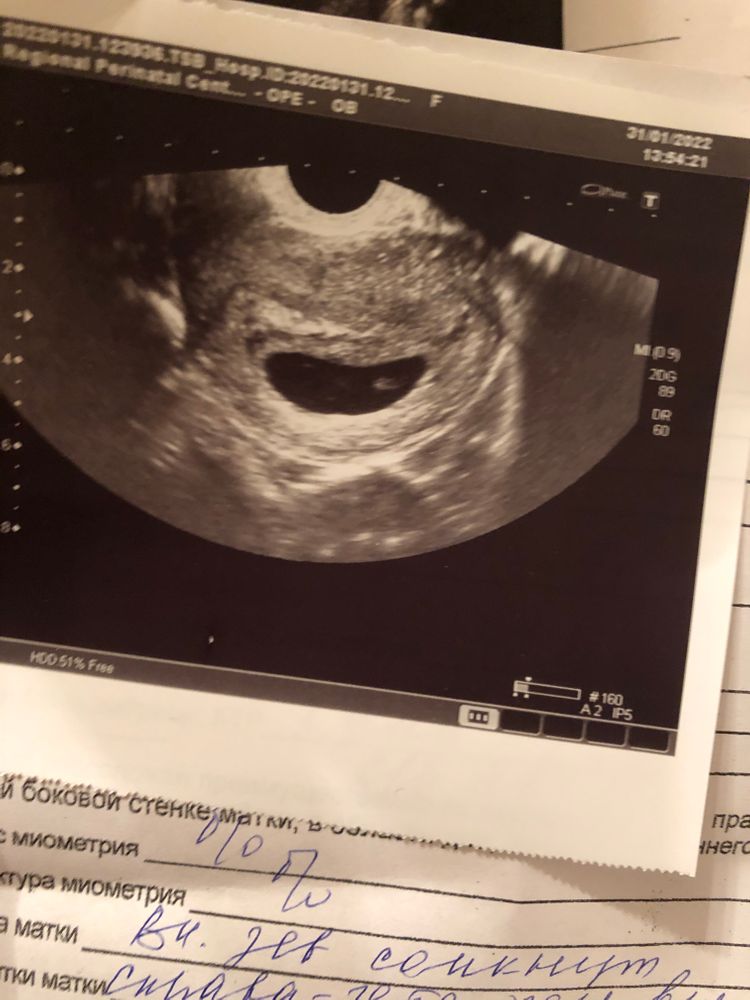

Последние месячные были 1.12, срок должен был быть 8 недель 6дн. На 7-й недели сильно болел живот, обратилась к дежурному геникологу в жк, т.к на учёт у нас ставят только с 8-у недели. Меня осмотрели, сказали все в порядке, назначали через неделю узи. Поставили на учёт, через пару дней пошла на узи, где мне говорят что не слышно сердцебиения. Спрашивают про симптомы тошнит, не тошнит и т.д, нет ли выделений(выделений нет, тошнить продолжает, сплю постоянно, живот не тянет, температуры нет, да и в целом ни единого признака замершей нету). Меня начали успокаивать и отправили к доктору, сказали есть вероятность что срок маленький, и ставят мне срок 5 недель 6 дней. Пошла к доктору, доктор сказала делать ХГЧ в динамике, и через неделю на повторное узи. Сделала на след день ХГЧ, не выдержала и через три дня(сегодня) я пошла на узи в другую клинику. Там мне сразу же сказали, что плод не развивается, и ставят срок 6-7 недель, так же размер эмбриона(ктр) при этом 3,9, а три дня назад был 3,22. Получается по размеру это и есть 6-7 недель, но плод увеличился же ведь… Меня и слушать сегодня не хотели, повели сразу к доктору, тот говорит надо делать срочно медикаментозный аборт. Я говорила про то, что второе ХГЧ ещё не делала, на это мне говорят, что уже бессмысленно его ждать все понятно, на данном сроке сердцебиение должно быть ясным. Записали на завтра на аборт. Я вся как в тумане, решила поехать и сделать ещё одно узи в другой клинике. Прихожу, начинаю объяснять, мол почему ставят разные сроки и размеры, спрашивать почему симптомы беременной у меня не пропали, а симптом замершей нет никаких. Говорят на это, что это аргумент. Пошли на само узи, тут же мне показывают что у меня два пя, и что у меня однозначно неразвитая беременность, ставят диагноз что у меня двойня и замершая. Я снова, как в тумане потерялась, забыла про все вопросы, в расстройстве, ушла. И только потом до меня дошло, что вероятно с меня хотели содрать деньги(за аборт и восстановление). Завтра на аборт не пойду, сделаю второе ХГЧ, и после на ещё одно узи. Надеюсь на чудо.

Прикреплю фото всех узи. И да, ХГЧ первое пришло там результат на 76037, результат в пределах нормы 7-9 недели.